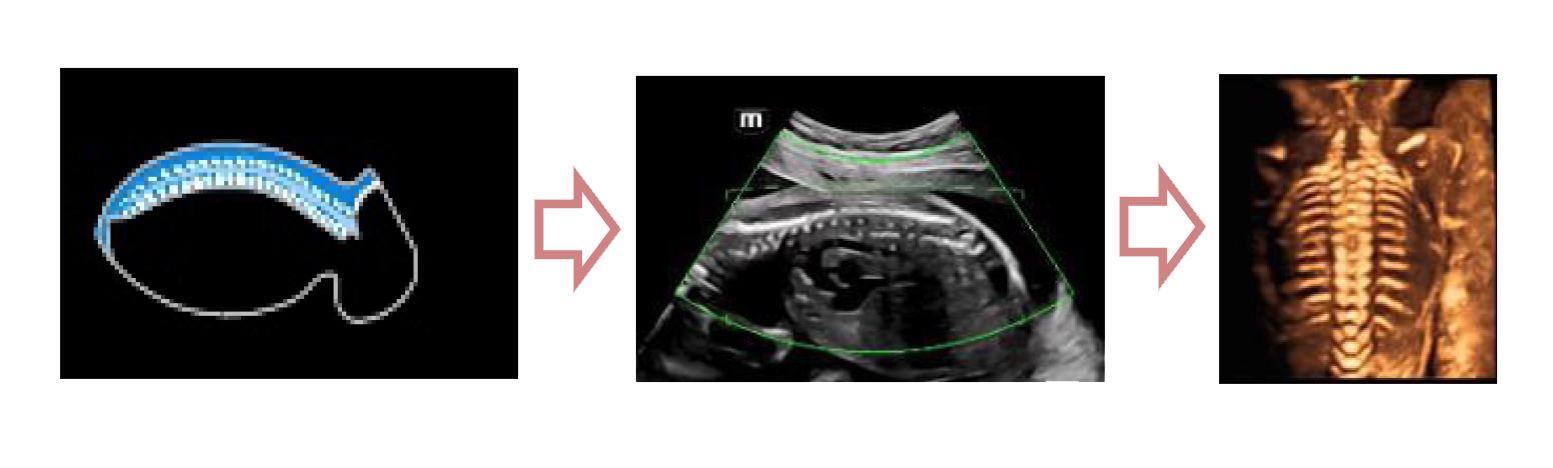

С легкостью получайте потрясающие 3D изображения позвоночника плода

- Автоматическое распознавание анатомии позвоночника плода

- Автоматическая подстройка зоны интереса и положения до оптимального

- Автоматический определение параметров рендеринга позвоночника

Место Smart Scene в технологии full-stack smartness